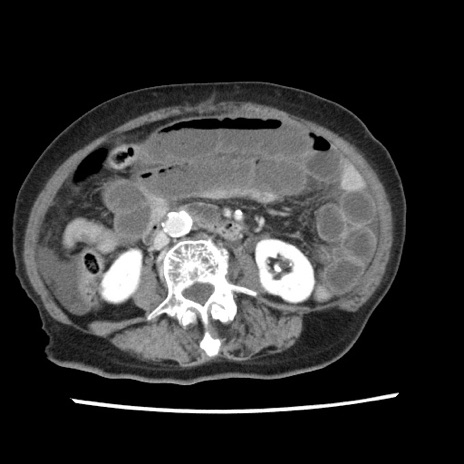

症例1(横断像)

【症例】80歳代女性

【主訴】腹痛

【現病歴】8時間前から腹痛あり来院。

【既往歴】糖尿病、脂質異常症、子宮体癌にて子宮全摘術

【身体所見】意識清明・会話良好だが腹痛で苦悶様、全腹部にわたって反跳痛と圧痛あり

【データ】WBC 13600、CRP 0.14、LDH 224、CK 90